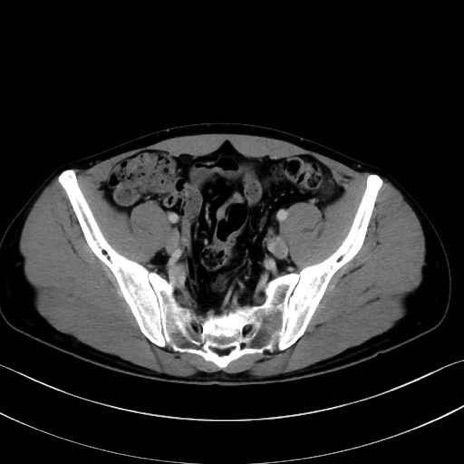

縫工筋(sartorius muscle) のCT画像の解剖

1. 体幹部(腹部・背部・後腹壁)の筋肉

2. 腸腰筋群と骨盤底筋

大腰筋 (Psoas major)

腸骨筋 (Iliacus)